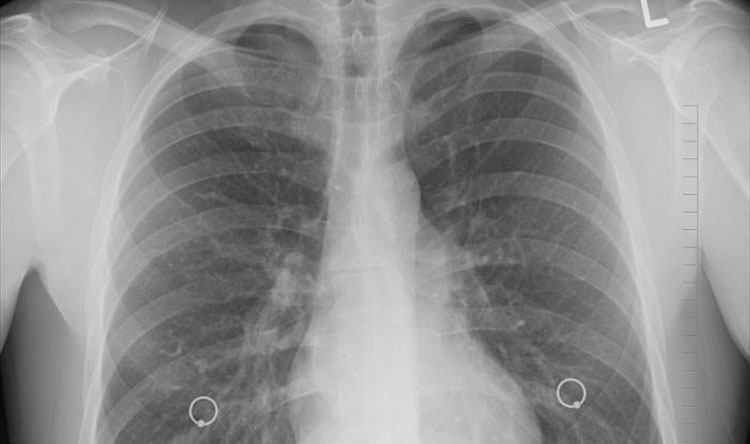

تشخيص سرطان الرئة ومراحله

سرطان الرئة التشخيص والعلاج Mayo Clinic مايو كلينك